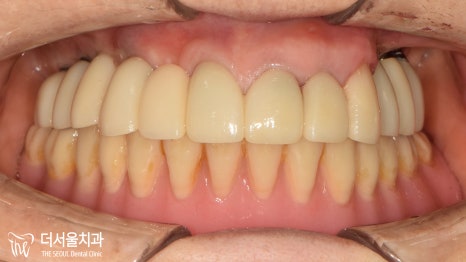

보내드리고 제작된 최종 보철을

체결한 사진입니다.

산성역치과에 처음 찾아오셨을 때와

다르게 많이 깔끔해졌습니다.

환자분도 역시 큰 변화를 느끼셨는지

수술 결과에 만족하셨습니다.

위에 부분적으로 쓰던 틀니의 불편함이

없어지고 편해졌다며 좋아하셨습니다.